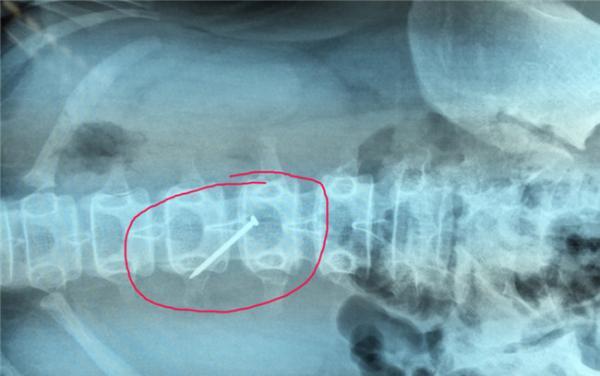

湖南七旬农妇腹痛30余年 体内取出450克重巨大结石